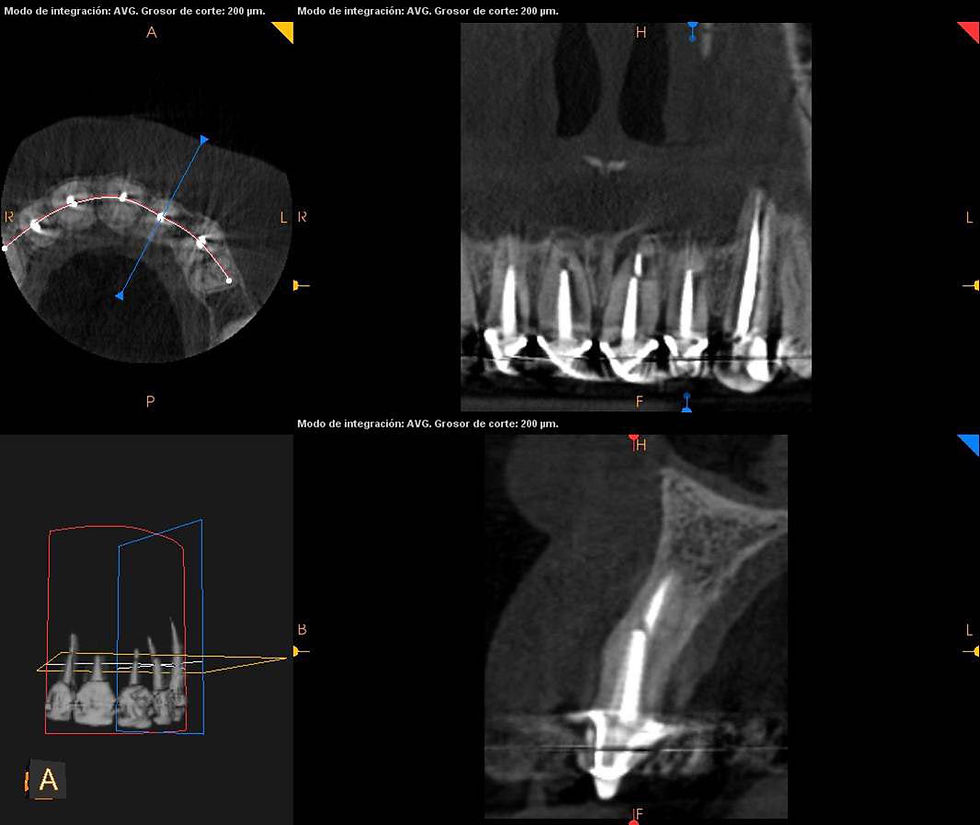

After the radiographic analysis we decide to extract the 4 incisors evidencing past multiple surgeries, some of which present infiltrations, apical granulomas and fistulas. It is also evident a fracture of the apical third of the root of the element 1.2, which seems to have already triggered a resorption process. GO TO THE VIDEO

CAD-CAM planning of the definitive prosthesis.